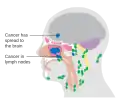

Cancer

Carcinoma of the maxillary sinus may invade the palate and cause dental pain. It may also block the nasolacrimal duct. Spread of the tumor into the orbit causes proptosis.[1]

-

Maxillary sinus cancer that has spread to the brain -

Maxillary sinus cancer that has spread to the lymph nodes